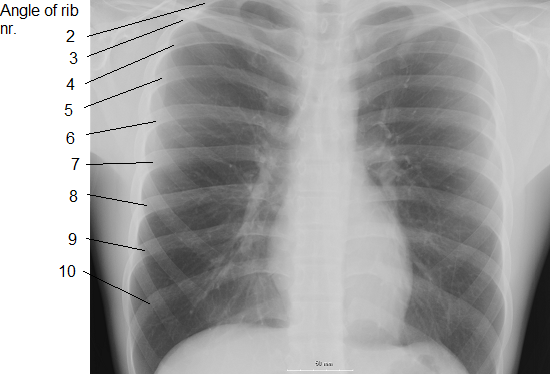

인간은 24개(12쌍)의 갈비뼈를 가지고 있다. 첫 7쌍은 참갈비뼈(true ribs)라고 하며, 복장뼈(sternum)에 갈비연골(costal cartilage)을 통해 관절한다. 나머지 5쌍은 거짓갈비뼈(false ribs)라 하며, 이 중 셋은 하나의 갈비연골을 통해 복장뼈에 연결되어 있고, 둘(11번째와 12번째 갈비뼈)은 뜬갈비뼈(floating ribs) 또는 척추갈비뼈라 하여 복장뼈와 관절하지 않는다. 일부 사람에게는 뜬갈비뼈 두 개 중 하나가 없거나, 세 개인 경우도 있다. 성경의 아담과 하와 이야기에 빗대어 남자가 여자보다 갈비뼈가 하나 적다고 생각하는 것은 잘못된 상식이다.[12]

사람은 12쌍(총 24개)의 갈비뼈를 가지고 있다. 앞쪽에서 늑연골로서 흉골과 결합하고 있다.

- '''참갈비뼈(진늑골)''' : 1번 ~ 7번 갈비뼈(7쌍)는 갈비연골(costal cartilage)을 통해 복장뼈(흉골, sternum)에 직접 연결된다.[6] 1번 갈비뼈는 짧고 평평하며 C자형으로, 흉골병에 부착된다. 2번에서 7번 갈비뼈는 아래로 내려갈수록 길어지고 덜 휘어진다.[7]

- '''거짓갈비뼈(가늑골)''' : 8번 ~ 12번 갈비뼈(5쌍).[12]

- 8번 ~ 10번 갈비뼈(3쌍)는 하나의 갈비연골을 통해 복장뼈에 간접적으로 연결된다.

- '''뜬갈비뼈(부유늑골)''' : 11번 ~ 12번 갈비뼈(2쌍)는 복장뼈와 연결되지 않고 척추에만 연결되어 있다.[2]

일반적으로 사람의 갈비뼈는 1번에서 7번 갈비뼈까지 길이가 증가하고, 12번 갈비뼈를 거쳐 다시 길이가 감소한다. 이러한 크기 변화와 함께 갈비뼈는 1번에서 9번 갈비뼈까지 점차 기울어지며, 12번 갈비뼈를 거쳐 덜 기울어진다.[7]